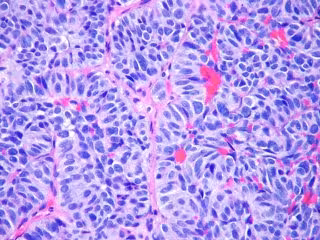

Foto: FLICKR/PULMONARY PATHOLOGY/ CC BY-SA 2.0